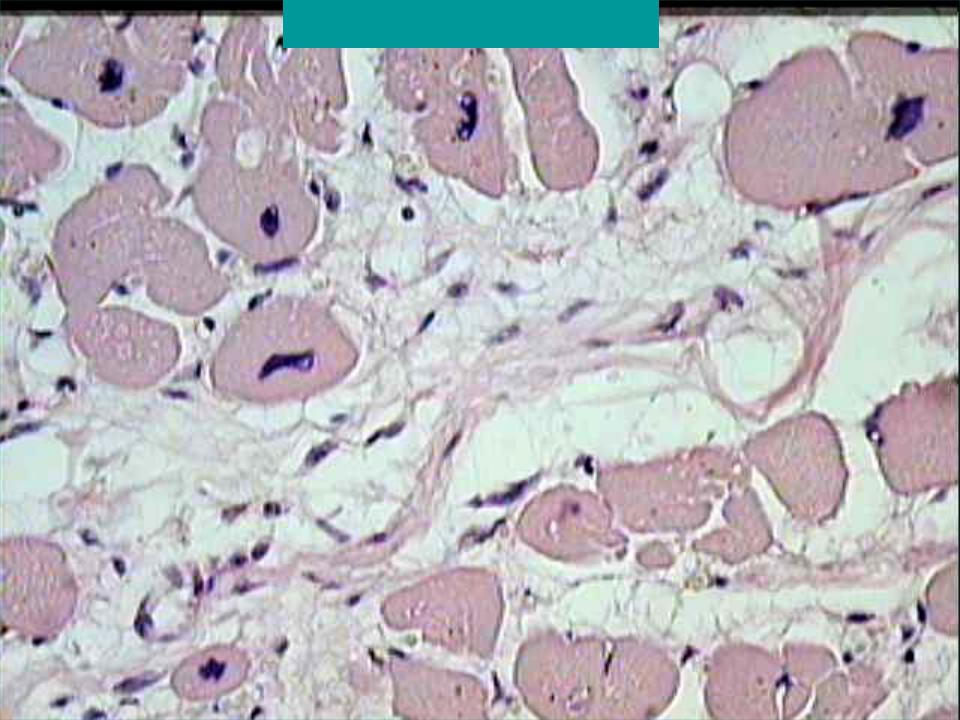

Межуточный миокардит: гистологические исследования